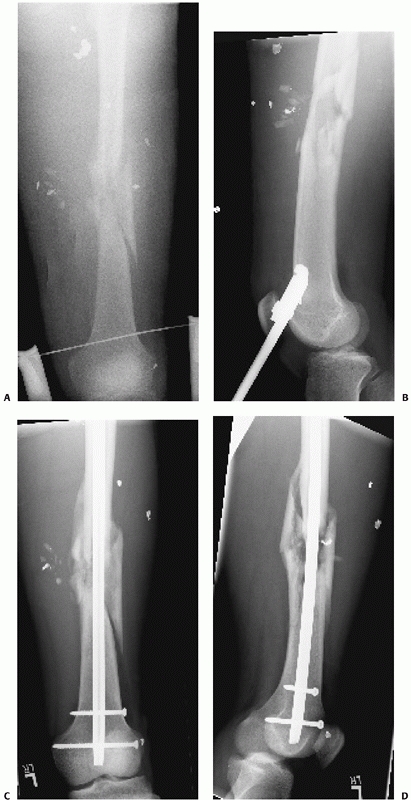

![]() |

FIGURE 50-9 A comminuted femoral diaphyseal fracture (A)

in a patient with multiple other injuries including a pulmonary contusion, liver laceration, and head injury. Temporary external fixation (B) was rapidly applied initially to provide stability and alignment. Conversion to an antegrade nail 7 days later resulted in uneventful healing (C). |